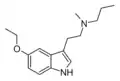

| 5-Ethoxy-DMT | artificial | 5-OCH2CH3 | CH3 | CH3 | 5-ethoxy-N,N-dimethyltryptamine | 855245-09-9 |

| 5-Ethoxy-MET | artificial | 5-OCH2CH3 | CH3 | CH2CH3 | 5-ethoxy-N-methyl-N-ethyltryptamine | |

| 5-Ethoxy-DET | artificial | 5-OCH2CH3 | CH2CH3 | CH2CH3 | 5-ethoxy-N,N-diethyltryptamine | |

| 5-Ethoxy-MPT | artificial | 5-OCH2CH3 | CH3 | CH2CH2CH3 | 5-ethoxy-N-methyl-N-propyltryptamine | |

| 5-Ethoxy-EPT | artificial | 5-OCH2CH3 | CH2CH3 | CH2CH2CH3 | 5-ethoxy-N-ethyl-N-propyltryptamine | |

| 5-Ethoxy-DPT | artificial | 5-OCH2CH3 | CH2CH2CH3 | CH2CH3 | 5-ethoxy-N,N-dipropyltryptamine | |

| 5-Ethoxy-MiPT | artificial | 5-OCH2CH3 | CH3 | CH(CH3)2 | 5-ethoxy-N-methyl-N-isopropyltryptamine | |

| 5-Ethoxy-EiPT | artificial | 5-OCH2CH3 | CH2CH3 | CH(CH3)2 | 5-ethoxy-N-ethyl-N-isopropyltryptamine | |

| 5-Ethoxy-DiPT | artificial | 5-OCH2CH3 | CH(CH3)2 | CH(CH3)2 | 5-ethoxy-N,N-diisopropyltryptamine | |

| 5-Ethoxy-DALT | artificial | 5-OCH2CH3 | H2C=CH-CH2 | H2C=CH-CH2 | 5-ethoxy-N,N-diallyltryptamine | |